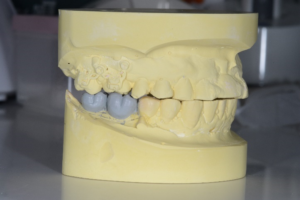

矯正的圧下は模型上でシミュレーションを行ってから行いました。圧下の経過を示します。

治療中

矯正用のアンカースクリューを用いて右上の奥歯を圧下しました。

技工士さんにインプラントの最終的なかぶせのイメージをワックスで製作してもらいました。